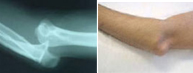

La articulación del codo tiene lugar entre el húmero y el cúbito y radio. Tiene lugar con mayor frecuencia en la segunda década de la vida. La separación traumática entre brazo y antebrazo es frecuente en el ámbito deportivo, especialmente en aquellos deportes que pueden provocar impactos sobre la mano con el codo en extensión. Ello es posible en artes marciales, futbol, baloncesto, y escalada entre otros.

Esta lesión no sólo compromete las estructuras óseas sino las ligamentosas y neurovasculares por lo que se requiere un meticuloso estudio en el servicio de urgencias para diagnosticar el grado de afectación tratándolo entonces adecuadamente.

En un primer momento la recolocación del codo en situación anatómica es primordial a través de un suave gesto y en algunas ocasiones bajo anestesia. Si a pesar de la congruencia articular, el codo se presenta inestable, puede ser necesario reforzar la estabilidad ósea con una intervención quirúrgica.